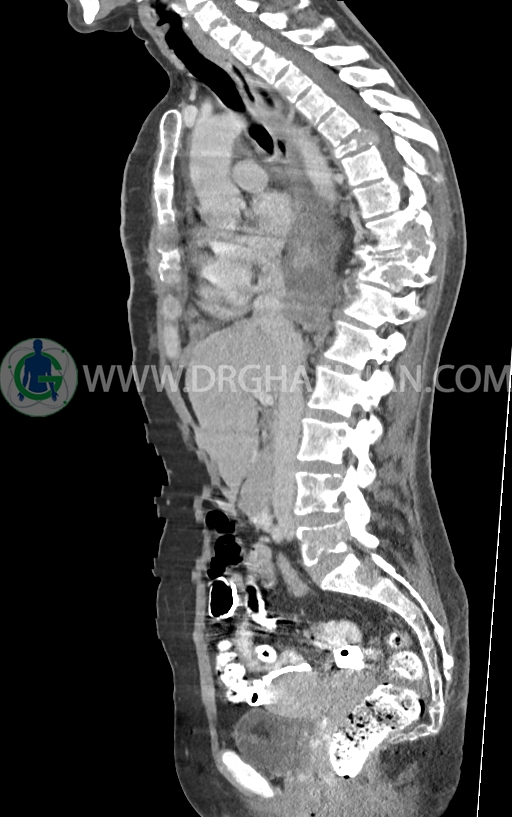

–ضایعات استخوانی لیتیک فراوان منتشر در تمامی طول ستون مهره و لگن رویت شدند که مطرح کننده متاستاز استخوانی می باشند.

–شکستگی پاتولوژیک در مهره های T6 , T10 , T11

–کیفوز موضعی در Level T10 , T11 در ستون مهره

–رتروپالشن شکستگی مهره T10 همراه با ایجاد تنگی کانال نخاعی